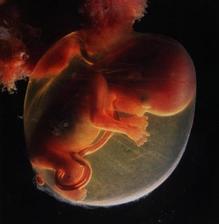

29.4. druhá KO u dr 7+3, 12,3mm a srdíčko bije

23.5. pro průkazku + odběr krve + utz 11+0 mimisek 4,2cm